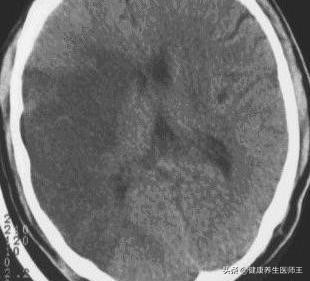

2.神经影像学 可以直观显示脑梗死的范围部位、血管分布、有无出血、病灶的新旧等。发病后应尽快进行CT检查,虽早期有时不能显示病灶,但对排除脑出血至关重要。多数病例发病24小时后逐渐显示低密度梗死灶,发病后2-15日可见均匀片状或楔形的明显低密度灶。大面积脑梗死有脑水肿和占位效应,出血性梗死呈混杂密度。病后2-3周为梗死吸收期,由于病灶水肿消失及吞噬细胞浸润可与周围正常脑组织等密度,CT上难以分辨,称为"模糊效应"。增强扫描有诊断意义,梗死后5-6日出现增强现象,1-2周最明是,约90%的梗死灶显示不均匀强化。头颅CT是最方便、快捷和常用的影像学检查手段,缺点是对脑干、小脑部位病灶及较小梗死灶分辨率低。